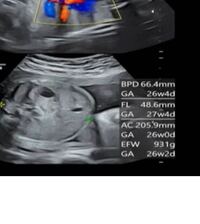

Aug 03, 09 · 妊娠8ヶ月まで、胎児の異常がわからない事はあるのでしょうか?友人の子は、妊娠8ヶ月まで障害がある事わからず、現在、重度の障害があります。妊娠8ヶ月目に脳に障害がある事と口唇口蓋裂が分かり、生まれてから 心臓に大きな穴がある事、目が見えない事もわかりました。エコーエコー写真でダウン症が判断できる エコー写真は、お腹の中にいる胎児の写真をとる技術です。 超音波を当てて撮影していくのですが、白くなっている部分は骨、黒くなっているものは羊水・血液です。 断面図だけを撮影する「2Dエコー」、立体的にSep 12, 17 · 妊娠26週目(26w0d~6d)のエコー写真とエピソード|妊娠7ヶ月 妊娠26週は妊娠7ヶ月の最終週です。 妊娠7ヶ月から健診の回数が2週に1回になり、より頻繁にエコー写真を見る機会が増えることでしょう。 赤ちゃんの性別がわかるようになり、出産準備にもそろそろ本腰をいれる頃です。 体重も増え、大きくなったお腹で移動するのは大変ですが、赤ちゃんに会える

妊娠26週目 26w0d 6d のエコー写真とエピソード 妊娠7ヶ月 Cozre コズレ 子育てマガジン